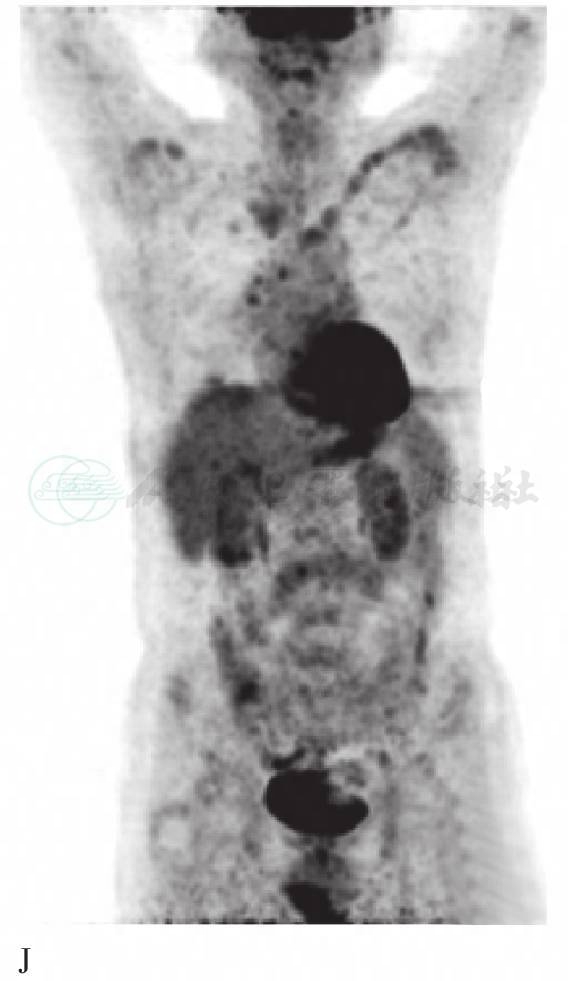

A. CT颅骨三维重建图;B. FDG PET脑3D图像;C. 18FECH PET脑3D图像;D. 18FECH PET图显示鞍区占位高代谢;E. CT鞍区图像;F. 18FECH PET/CT显示鞍区占位高代谢灶;G. FDG PET显示鞍区占位高代谢;H. CT鞍区图像;I. FDG PET/CT显示鞍区占位高代谢灶;J. FDG PET 3D显示锁骨等多处高代谢灶;K. 18FECH PET 3D显示双侧锁骨等多处高代谢灶

18FECH PET/CT提示颅骨多发骨质破坏,病变区SUVmax为5.7,与大脑皮层的SUVmax比值为14.3;右侧上颌窦和鞍区软组织密度影的SUVmax为5.1~5.8(图1D、E、F),与大脑皮层的SUVmax比值为12.8~14.5;左侧的胸锁关节和双侧肩关节骨质破坏,病灶的SUVmax为4.0。FDG PET/ CT提示颅骨多发骨质破坏,病变区SUVmax为2.8,与大脑皮层的SUVmax比值为0.4;右侧上颌窦和鞍区可见软组织密度影(图1G、H、I),病灶SUVmax为4.3~6.0,与大脑皮层SUVmax比值为0.7~0.9;左侧胸锁关节和双侧肩关节骨质破坏,病灶的SUVmax为2.2。